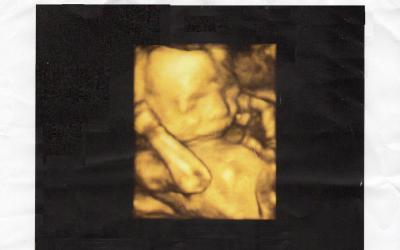

so hab es auch mal geschafft vom donnerstag auch mal ein 4d foto die ärztin war mal so nett und hat eins ausgedruckt.

der kleine ist jetzt 21 cm und 350 gramm schwer